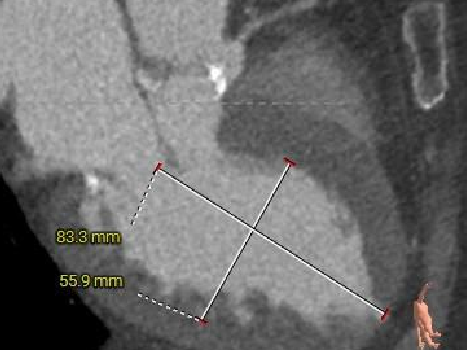

术前CT分析(76岁,女性)

▶ Type1型二叶式主动脉瓣(L-R),瓣叶增厚,重度钙化,钙化分布不均匀,无窦钙化延申至STJ以上,LVOT偏直筒型。

▶ 左右冠脉开口高度尚可,左窦瓣叶切线测量距离>冠脉开口下缘到根部距离。

▶ 心室腔内径尚可,心室壁厚度可,心尖尚可。

▶ 瓣环水平夹角72°,横位心,主动脉弓角、弓距尚可。

主动脉根部测量